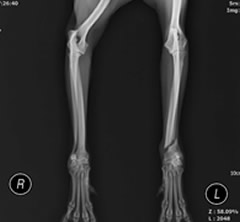

前腕骨骨折整復

前腕骨(橈尺骨)遠位骨折

整形外科領域でも癒合不全や癒合遅延といった骨の治癒過程でのトラブルが非常に多い部位です。